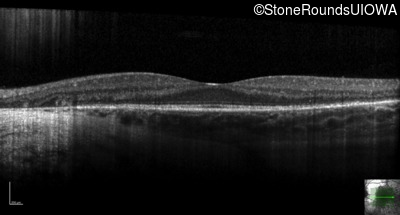

Age at visit: 32 years